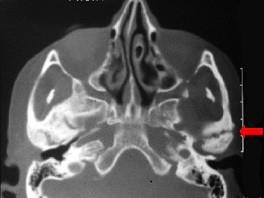

患儿,5岁,外伤后逐渐出现张口困难,咬合关系错乱,髁突动度减弱,外观及X 线检查结果如图。最可能的诊断是 ( )

患儿,5岁,外伤后逐渐出现张口困难,咬合关系错乱,髁突动度减弱,外观及X 线检查结果如图。最可能的诊断是 ( )![]()